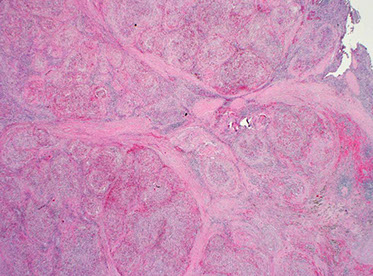

Reactive follicular hyperplasia (arrow to focal paracortical hyperplasia) [2]

Reactive Follicular Hyperplasia (RFH). Follicles (B-cell compartment) have varying size and are well spaced from one another. There is a nice capsule and subcapsular sinus. In medullary compartment where plasma cells and memory B-cell live, the sinuses are open and patent. Note the relative abundance of the paracortex compared to the cortex, which is an important feature for B9 LNs.

Hyperplastic lymphoid follicle. Germinal center with sharply demarcated mantle zone (solid blue arrow). Dark zone of GC with starry-sky pattern (open blue arrow) and light zone (open black arrow) with small centrocyte predominance [2]

High magnification of GC with centroblasts (solid blue line) mixed with histiocytes with clear cytoplasm with nuclear fragments (open black line) and frequent mitoses (curved black line)